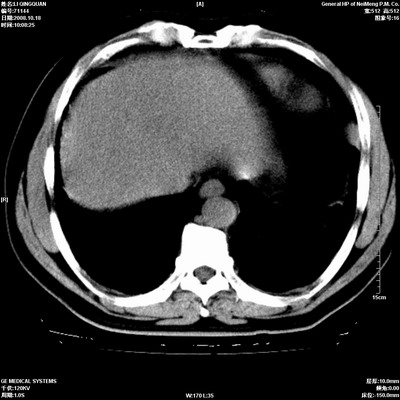

以下是引用duguo在2008-10-19 13:59:00的发言:[br]左肺上叶支气管狭窄,首先考虑中心型肺癌伴阻塞性肺炎\\肺不张.

以下是引用ybing在2008-10-19 12:58:00的发言:[br]左肺上叶阻塞性炎症-建议支气管镜进一步检查除外中央型肺癌

以下是引用随光逐影在2008-10-19 14:31:00的发言:[br]考虑左肺中央型肺癌并左肺上叶阻塞性肺炎,肺不张。